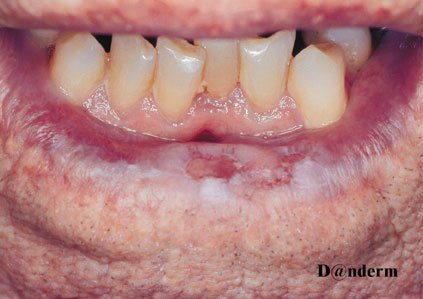

Kolczystokomórkowy rak skóry na dolnej wardze. Dzięki uprzejmości dr Veiena/Danderm

- Obraz kliniczny to zwykle hiperkeratotyczne ognisko chorobowe, płaskie owrzodzenie z obwódką lub keratotyczny guzek z czopem rogowym, owrzodzeniem lub bez niego.

- Rozmiar od kilku milimetrów do kilku centymetrów